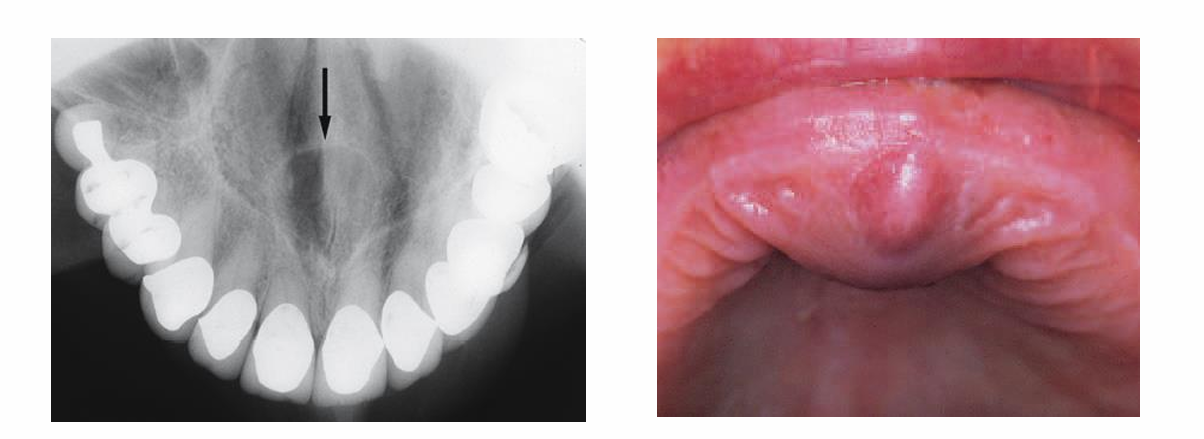

cyste van de ductus nasopalatinus (niet-odontogeen)